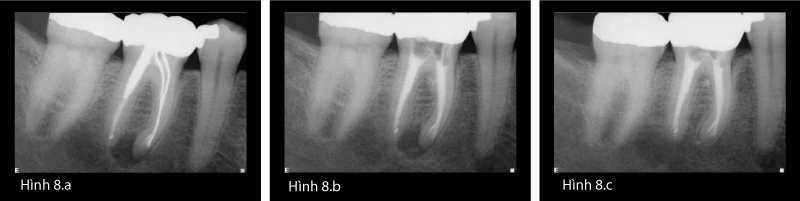

Case dùng côn bạc sau đây (Hình 8a-c), với 1 chốt lớn phía xa và sự di chuyển chóp ở chân gần, chứng minh sự lành thương thành công của bệnh sau điều trị khi việc khử khuẩn hoàn toàn đã được thực hiện xong. Case này minh họa lí do mà điều trị tủy lại là lựa chọn điều trị đầu tiên cho bệnh lý sau điều trị.